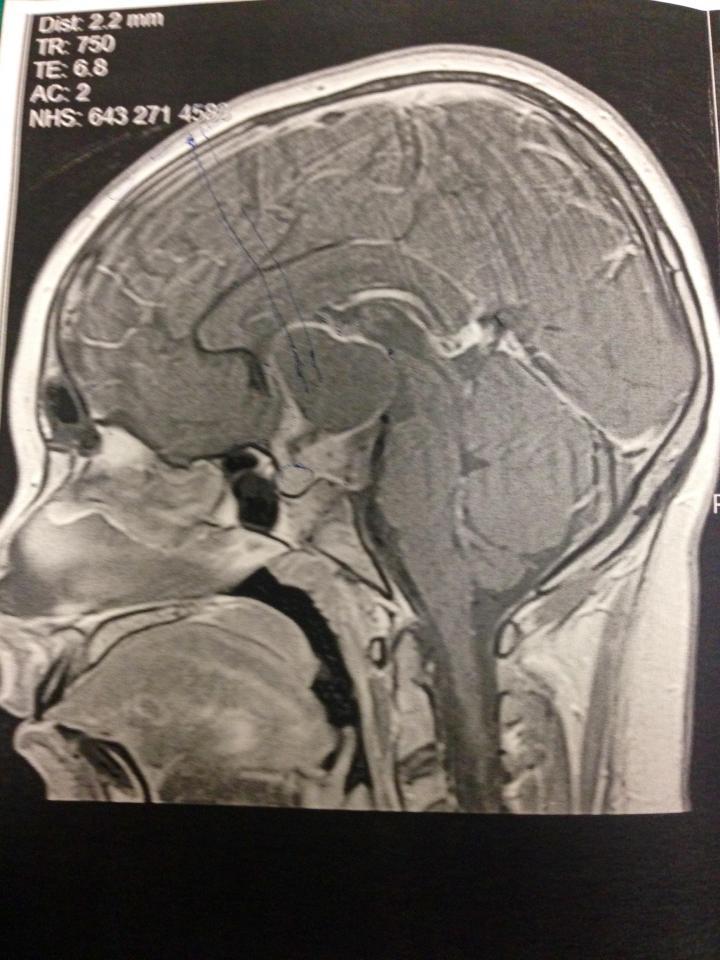

Adoleshentja skoceze nga Peterhead, në Aberdeenshire, siç shkruan “The Sun”, kishte probleme me shikimin dhe vuante vazhdimisht nga dhimbjet e kokës. Fillimisht i’u tha se ishin probleme normale për moshën e saj, por pak kohë më vonë, analizat e thelluara zbuluan një masë tumorale në trurin e saj.

Emma u operua dhe një pjesë e madhe e tumorit i’u hoq, por jo e gjitha, ndërsa metastazat u përhapën me shpejtësi deri sa i morën jetën.